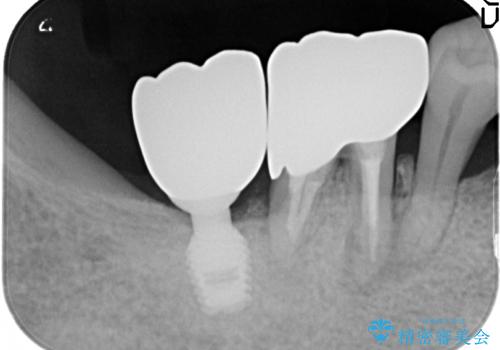

歯周病でぐらぐらになってしまった奥歯を抜歯し、残る骨の高さを鑑みてショートインプラントを選択しました。

インプラントの種類:Bicon

かぶせ物の種類:Bellezza